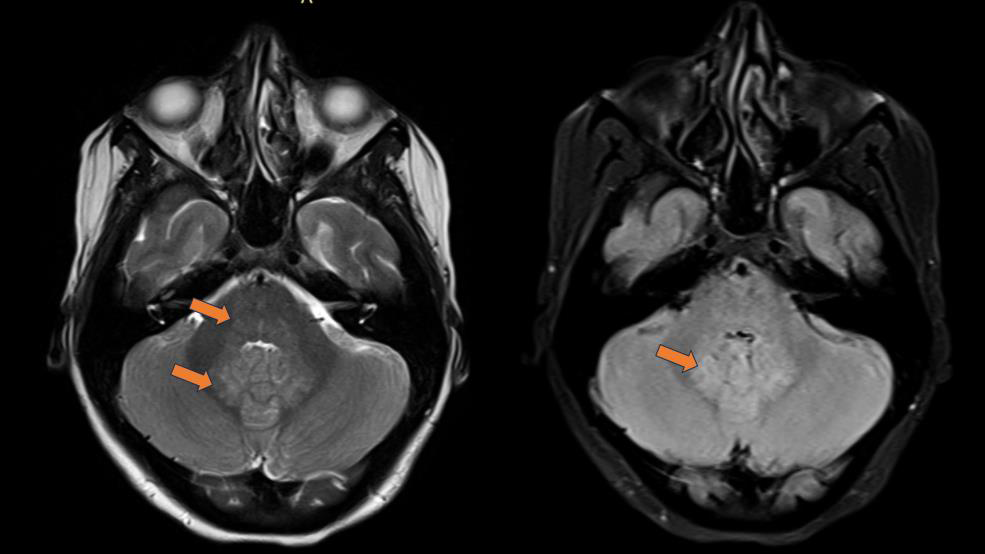

Figure 2:MRI Brain(T2/FLAIR): Bilateral hyperintense lesions involving

superior colliculus of midbrain.

documented in case series and radiological reviews. Opsoclonus

and dysarthria point toward cerebellar and brainstem involvement.